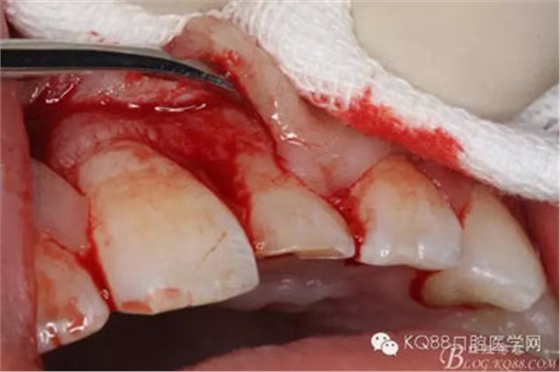

圖7.翻瓣、注意是全厚瓣。

圖8.翻開牙齦粘膜瓣,可見左乳Ⅰ根方骨面隆起